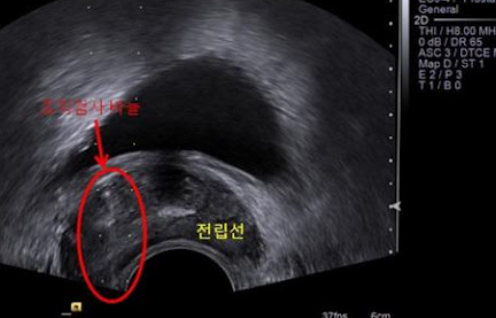

(3) 영상검사

- MRI나 초음파를 통해 전립선 내부와 주변 조직 상태를 확인합니다.

(4) 조직검사

- 의심 부위에서 조직을 채취하여 암세포 존재를 확인합니다.

- 전립선암 확진은 이 조직검사를 통해 이루어집니다.